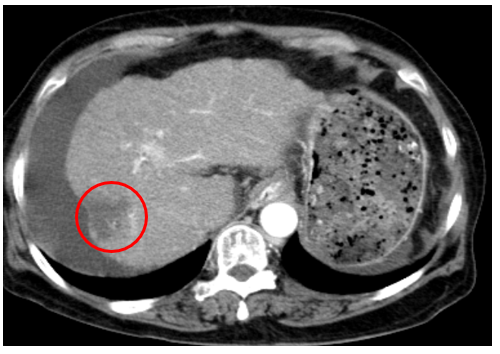

Chụp cắt lớp vi tính ổ bụng

Gan: Biến đổi hình thái, phì đại HPT I, bờ gan không đều. Nhu mô gan phải có khối giảm tỉ trọng kích thước 30x31mm, ranh giới không rõ, co kéo bao gan lân cận, tỷ trọng hỗn hợp, gồm phần tăng tỉ trọng của vật liệu nút mạch, phần tỷ trọng tổ chức vùng ngoại vi, sau tiêm ngấm thuốc mạnh thì động mạch, thải thuốc thì tĩnh mạch

Dịch quanh gan 22mm. Dịch tự do ổ bụng dày nhất 28mm

Hình ảnh u gan phải sau điều trị hiện còn phần ngấm thuốc sau tiêm (Vòng tròn đỏ), tăng nhẹ kích thước so với lần trước